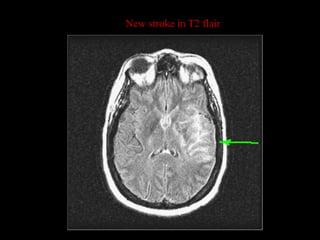

New stroke in T2 flair

New stroke inT2 flair

• #41 New strokes usually show up as white on T2.